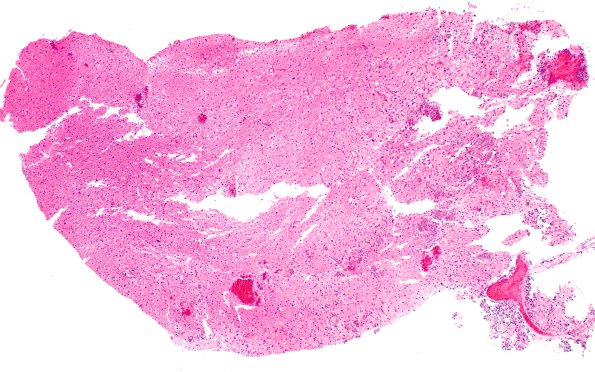

Washington University Experience | NEOPLASMS (GLIAL) | High-Grade Astrocytoma with Piloid features (HGAP) | 3B1 HGAP (Case 3) H&E 4X

The tumor appears hypocellular in this low magnification image of the neurosurgical specimen. (H&E)